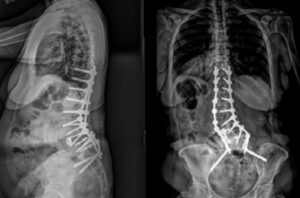

Dr. Jay Turner performs T10-pelvis fixation utilizing iFuse 3DTM in the Bedrock trajectory to provide multiple points of SI joint fixation.